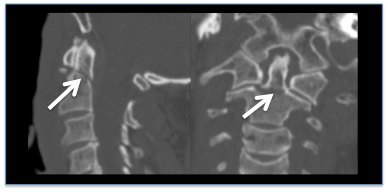

Reconstrucción de TC que muestra una fractura sin desplazamiento de la apófisis odontoides